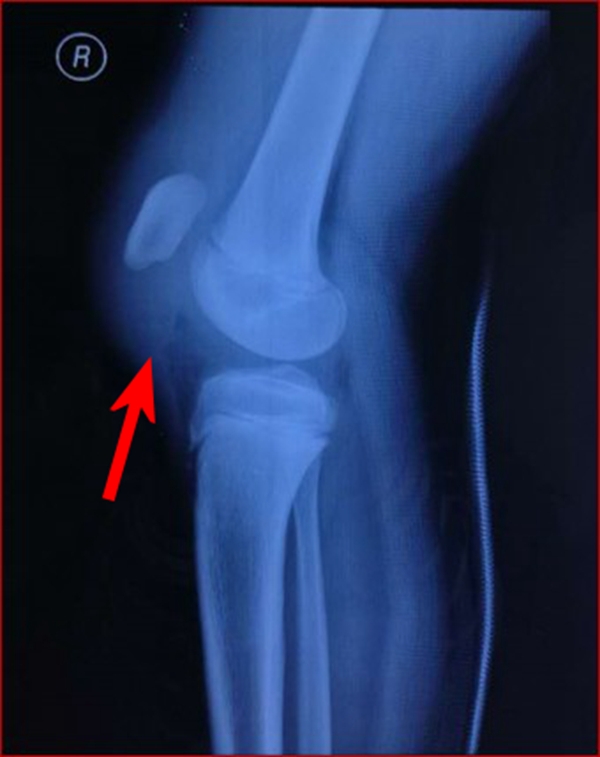

图3 受伤后3周MRI

1.髌骨上、下极的斑片、点状薄层骨组织影像或半环、新月形骨块阴影,同时还应注意髌骨有否高位、低位及髌韧带、股四头肌腱软组织影是否松弛。

2.X线片无骨性组织显影时,应予以MRI扫描。